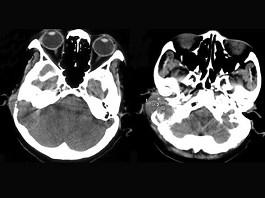

问题 女,56岁,右侧中耳术后发现右外耳道新生物一年,PE:右外耳道内段被新生物充满,CT如图所示,应诊断为 ( )

选项 A、听神经瘤 B、中耳结核 C、中耳癌 D、颈静脉球瘤 E、胆脂瘤

答案 C